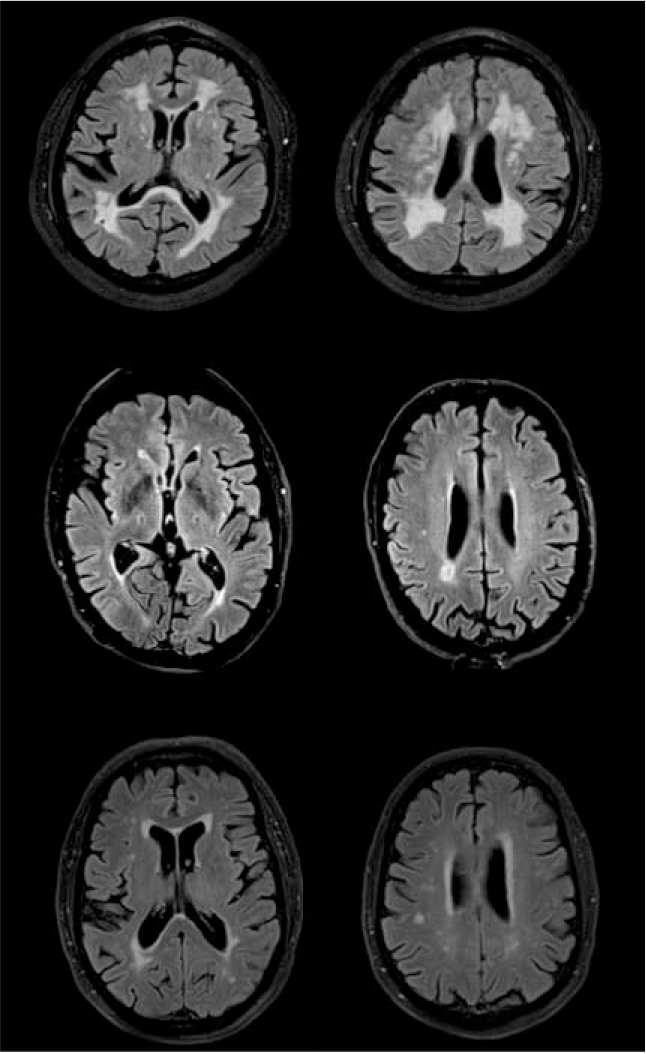

Lacunes are small, round or oval subcortical infarcts from 3 to 20 mm in size. They may be clinically silent, but may be accompanied by a history of transient ischaemic attack or stroke. Lacunar infarcts in thalamus can cause prominent cognitive problems. At least two lacunes are required for a diagnosis of vascular dementia. There is good evidence that lacunar infarcts can form a substrate for vascular dementia. They are often multiple and bilateral and are associated with disease affecting the small arteries and arterioles subserving deep grey and white matter (Fig. 2).

FIG 2 Magnetic resonance images of vascular damage: (a) 81-year-old patient (MMSE = 21/30)with dementia and diffuse white matter changes; (b) 76-year-old patient (MMSE = 20/30) with bilateral lacunar infarcts; (c) 77-year-old cognitively healthy control (MMSE = 30/30) with mild white matter changes. Images were acquired with a FLAIR sequence in a 3T scanner.

A number of types of small vessel disease are seen on imaging (Fig. 2). White matter hyper-intensities appear bright on T 2-weighted and FLAIR MRI images. When seen in CT, they appear dark and are referred to as hypodense areas or leukoaraiosis. They become more common with increasing age and are associated with cognitive impairment. As they are so commonly seen, the NINDS–AIREN criteria set an arbitrary cutoff that at least 25% of the total white matter should be affected for a diagnosis of vascular dementia. White matter hyperintensities can be seen around the lateral ventricles, often starting at the poles, and in subcortical areas, although these two types of distribution are thought to have different aetiologies. They are often rated either by eye or by using an automated process as mild (punctiform), moderate (beginning confluent) or severe (confluent) (Reference Scheltens, Erkinjuntti and LeysScheltens 2000).

We are extremely grateful to Dr Giovanna Zamboni for providing the images in Fig. 2.